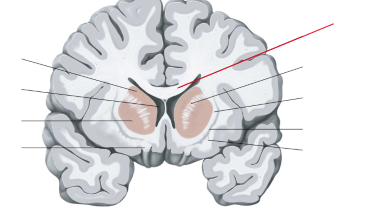

fissura longitudinalis cerebri

nucleus caudatus

putamen

globus pallidus

capsula interna (corona radiata)

capsula externa

capsula extrema

hippocampus

amygdala

fornix

laterale ventrikels (I en II)

septum pellucidum